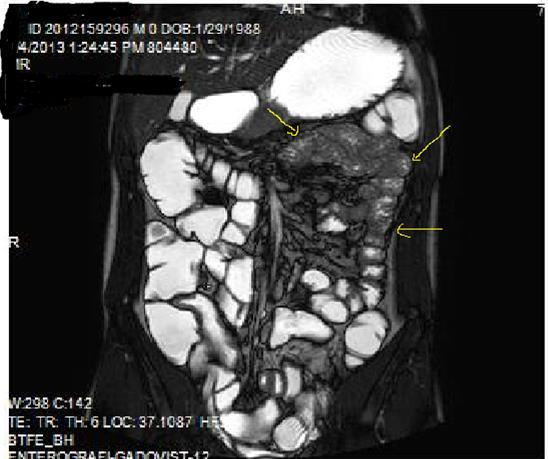

Figure 1a.Diffuse mucosal involvement and increased wall thickness with loss of valvula conniventes in the ileal segments on T2W coronal images after OCA administration, seen on 30 years old female with moderate Crohn’s disease.

Figure 1b.Diffuse bowel wall enhancement in the small intestine due to Crohn’s disease on the Post-contrast T1W coronal sequence.